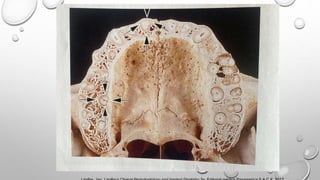

Imagen

mandíbula y

señalar

proceso

alveolar y

cuerpo basal